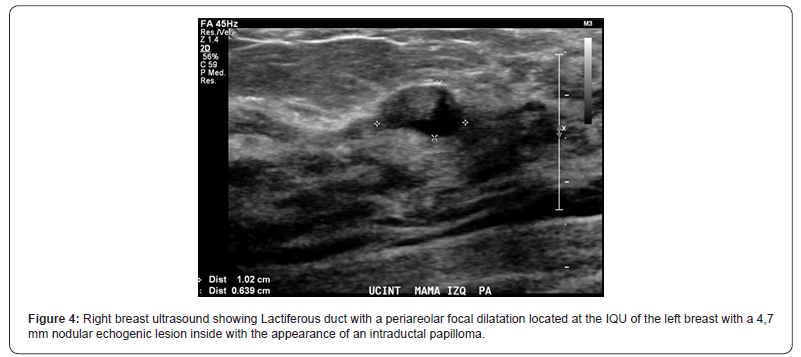

We present the case of a healthy 37 years-old women, with self-detected right breast nodule with 6-months evolution, that was progressively growing and sensitive at touch, associated with erythema and pruritus. She had a familial history of two cousins with breast cancer. At physical exam, there was a hard tumor of approximately 60 x 50 x 30mm at the upper quadrants union (UQU) of the right breast and another 20mm nodule, difficult to separate from the bigger tumor, toward the upper- outer quadrant (UOQ). She was studied with a contrasted mammography that showed a 45mm round-shaped nodule with spiculated edges and early enhancement with contrast, at the UQU (BIRADS-5) and a second 22mm well delimited and moderate enhancing nodule at the upper outer quadrant (UOQ) of the right breast (Figure 1) without invasive-suspected lesions at the left breast. The breast ultrasound demonstrated a 42mm heterogeneous, lobulated mass with imprecise limits and hypoechoic central portion associated with microcalcifications at the UQU of the right breast (Figure 2), a solid oval-shaped well delimited and vascularized 15mm nodule at the UOQ (Figure 3). There was also a 10mm solid-cystic lesion at the inner-quadrants union (IQU) of the left breast (Figure 4). A core biopsy of the two right breast masses was then performed, demonstrating a biphasic fibro-epithelial lesion. The patient underwent a partial bilateral mastectomy of the three lesions, two of them previously marked under ultrasound guidance. The definitive biopsy demonstrated that the lesion of the UQU of the right breast - hour 12, corresponded to a fibromatosis (Figures 5 & 6), and that the other lesion of the UOQ of the right breast was a phyllodes tumor with signs of benignity (Figure 7). In the left breast, an intraductal papilloma was found (Figure 8). The case was discussed at the Oncologic Committee, deciding to follow-up the patient at 6 months with breast ultrasound and contrasted mammography and to offer chronic treatment with celecoxib.